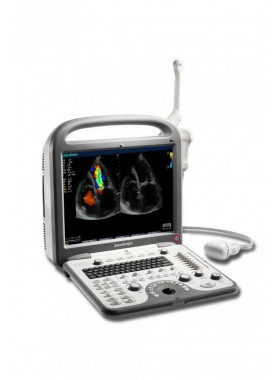

SONOSCAPE S2N (ВЕТ)

Компактная и хорошо оснащенная система SonoScape S2N (ВЕТ) формирует ультразвуковые изображения с высокой точностью и детализацией. Прибор весит всего 4,5 кг вместе с батареей. Его можно использовать в клинике, в машине скорой помощи, при выезде к пациентам. Этот бюджетный УЗИ-сканер строит цифровые изображения с высоким разрешением, в том числе в режиме реального времени 3D-Live. Как официальный дилер SONOSCAPE MEDICAL CORPORATION наша компания поставляет медтехнику «СоноСкейп» по доступным ценам.

Особенности SonoScape S2N (BET)

С портативным ультразвуковым сканером SonoScape S2N (ВЕТ) вы получаете высокоточные УЗИ в стационарных и полевых условиях обследования. Используйте его для общих и кардиологических исследований в клинике, больнице, медицинском центре или в машине скорой помощи, дома у пациентов. Он удобно и быстро настраивается, интерфейс аппарата интуитивно понятен. Опции многочисленны и регулируются в широких диапазонах. Изображения получаются четкие, яркие. С ними вы можете уверенно ставить диагноз.